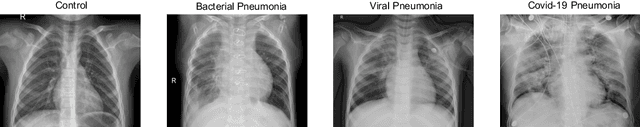

Abstract:Respiratory diseases kill million of people each year. Diagnosis of these pathologies is a manual, time-consuming process that has inter and intra-observer variability, delaying diagnosis and treatment. The recent COVID-19 pandemic has demonstrated the need of developing systems to automatize the diagnosis of pneumonia, whilst Convolutional Neural Network (CNNs) have proved to be an excellent option for the automatic classification of medical images. However, given the need of providing a confidence classification in this context it is crucial to quantify the reliability of the model's predictions. In this work, we propose a multi-level ensemble classification system based on a Bayesian Deep Learning approach in order to maximize performance while quantifying the uncertainty of each classification decision. This tool combines the information extracted from different architectures by weighting their results according to the uncertainty of their predictions. Performance of the Bayesian network is evaluated in a real scenario where simultaneously differentiating between four different pathologies: control vs bacterial pneumonia vs viral pneumonia vs COVID-19 pneumonia. A three-level decision tree is employed to divide the 4-class classification into three binary classifications, yielding an accuracy of 98.06% and overcoming the results obtained by recent literature. The reduced preprocessing needed for obtaining this high performance, in addition to the information provided about the reliability of the predictions evidence the applicability of the system to be used as an aid for clinicians.